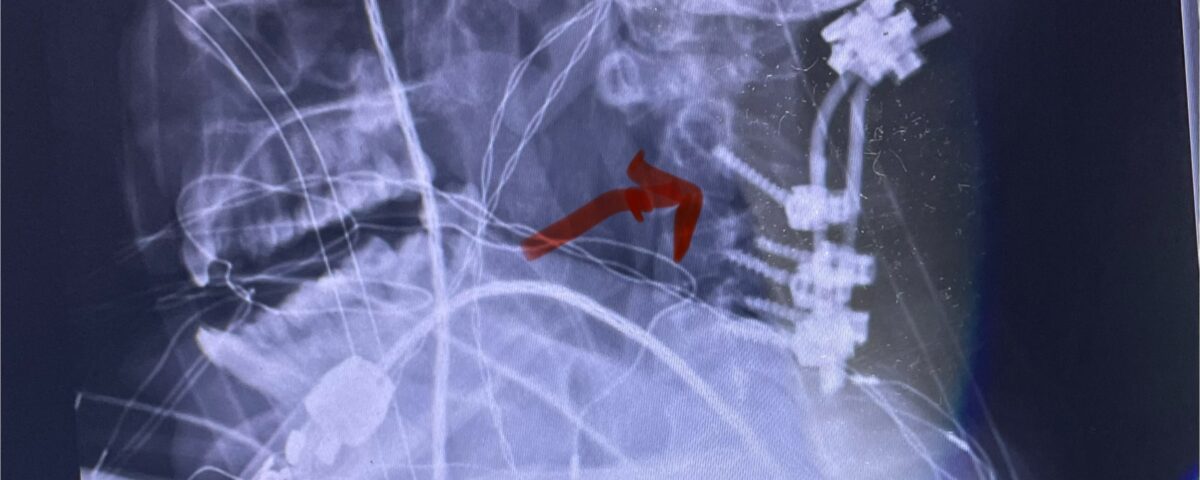

Cervical x-rays revealed a significantly increased atlanto-axial interval (Fig. 5) On review of her imaging studies it was noted that the right C2 isthmus was very thinned by the vertebral foramen (Figs 6a, b, and c) which would make an attempt at placing a C2 pars screw dangerous. A decision was made to perform an occipital-cervical fusion because only possible unilateral fixation and an extensive C1 laminectomy to be performed eliminating a fixation point if a more traditional C1-C2 was performed. Even if C1 lateral mass screws were able to be placed one could only perform a unilateral screw construct fixation to C2. We performed an occipital cervical fusion down to C4 to get enough inferior fixation and C1 laminectomy. The decompression went well. We placed a left unilateral pars screw and bilateral C3 and C4 lateral mass screws. We placed three 12 mm screws in the midline keel (Fig. 7). Postoperatively the patient had all around improvement in her symptoms and did not qualify for rehab. Her post op films at 6 weeks (Fig. 8)

Fig. 7: Intraoperative photograph demonstrating occipital-cervical construct and C1 laminectomy (blue dot). Note the 3 screws in the midline keel (blue arrow)

Fig. 8: Intraoperative photograph demonstrating occipital-cervical construct and C1 laminectomy (blue dot). Note the 3 screws in the midline keel (blue arrow)